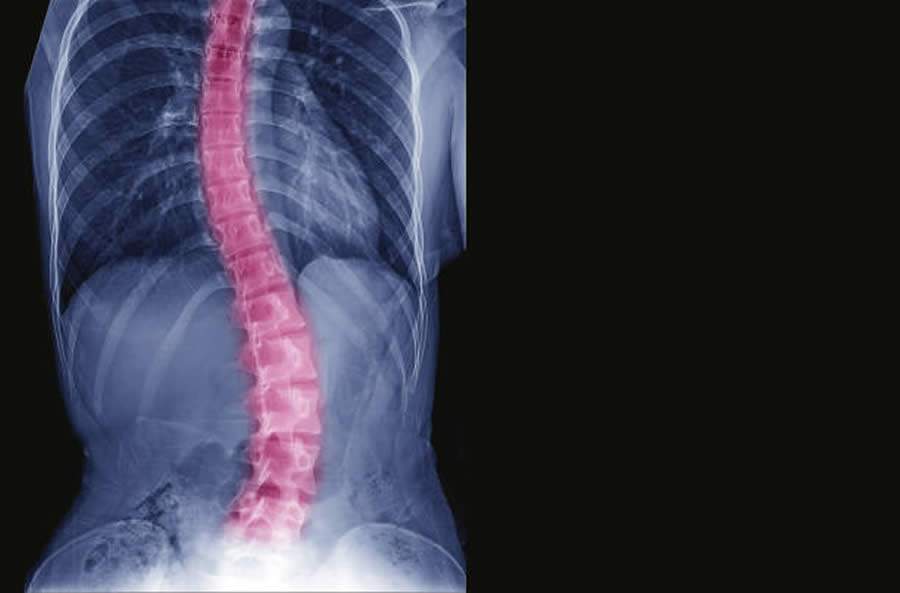

“A Escoliose Idiopática Adolescente (EIA) é uma curvatura anormal da coluna para um dos lados do tronco, trata-se de um desvio de coluna progressivo que pode ou não ser acompanhado de rotação das vértebras. Em 80% dos casos, as causas são desconhecidas e, por isso, ela é descrita como escoliose idiopática”, alerta Dr. Álynson Larocca Kulcheski, médico ortopedista do Hospital VITA, especialista em coluna.

Segundo o ortopedista, é a deformidade mais frequente da coluna. A coluna adquire um desvio das curvas naturais, que pode desencadear um desequilíbrio funcional. O desvio mais frequentemente observado é no plano frontal (visto de frente ou de costas) e nota-se uma inclinação da coluna para um dos lados.